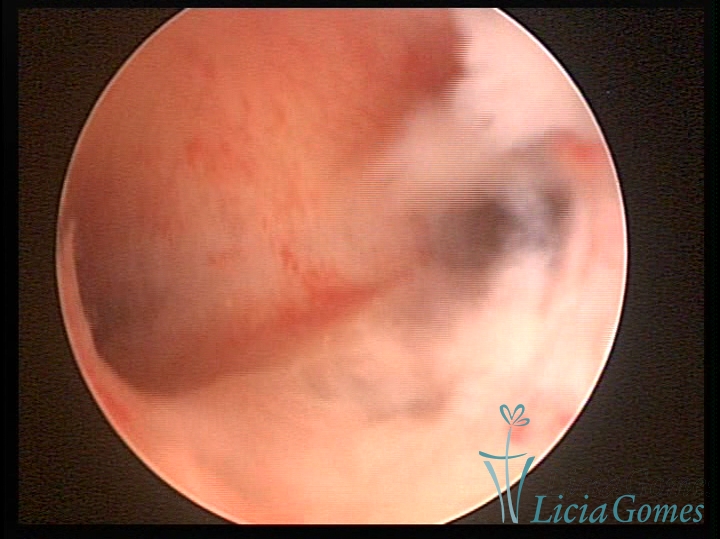

Bicornuate uterus

Malformation in which there is the lack of the flat portion of uterine fundus due to the lack of fusion on the proximal portion of paramesonephric ducts. The uterine fundus has two narrowed spaces in a divergent oblique angulation. It may be complete, from the fundus to the cervix; or partial, completely dividing the uterine cavity.

The tilted uterus which presents the most difficult hysteroscopic diagnosis occurs when there is only a small indentation of the uterine fundus.